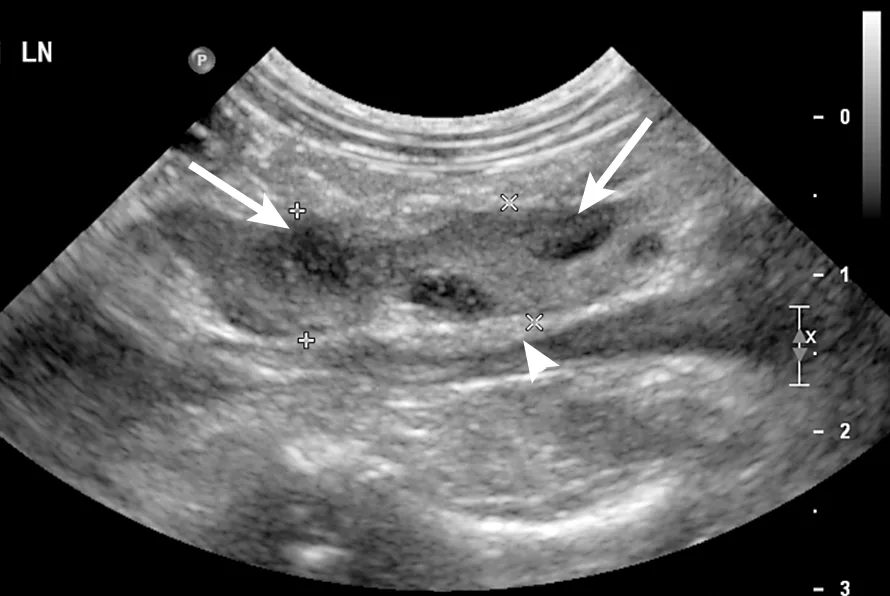

Abdominal ultrasonography revealed the presence of multiple enlarged, heterogeneous, and rounded cranial mesenteric lymph nodes (Figures 1, above, and 2). These findings were suggestive of round cell neoplasia, lymphadenitis (infectious or noninfectious), or reactive lymphadenopathy. There was a small amount of free abdominal fluid, which was sampled and submitted for analysis; this was compatible with a nonseptic suppurative exudate. Culture results of the fluid were negative. Fine-needle aspirates and cytology of the abdominal lymph nodes were consistent with neutrophilic lymphadenitis (Figure 3). No infectious agents were seen. The rest of the abdominal ultrasound was unremarkable.

Ultrasound image of a jejunal lymph node. A moderately enlarged lymph node with a lobulated heterogeneous appearance and ill-defined hypoechoic patches can be seen (arrows). The mesenteric fat around the lymph node was diffusely hyperechoic (arrowhead).